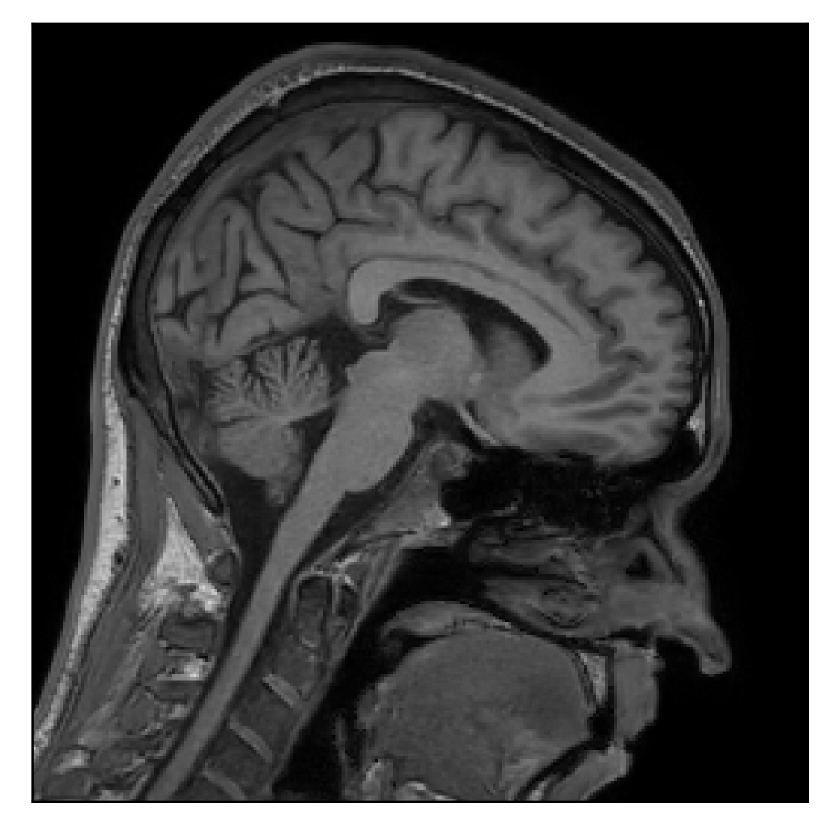

We consider three levels of motion corruption: (i) the volunteer moves once, (ii) the volunteer moves twice, and (iii) the volunteer moves five times. The volunteer is instructed to change its head position every time it is prompted to do so, and maintain that position in between instructions. We use T2-FLAIR-weighted contrasts as corrupted scans, with T1-weighted contrast as a reference (see Table 1 for further details). The corrupted acquisition employs randomized sampling.

| Section 3.1, Figure 4 | Sagittal | 25.78 | 27.76 | 0.7263 | 0.7816 |

| Coronal | 28.19 | 29.73 | 0.7847 | 0.8244 | |

| Axial | 27.79 | 29.70 | 0.8104 | 0.8362 | |

| Section 3.1, Figure 4 | T2-FLAIR | Completely corrected | Some blurring | No additional artifacts | Good grey white matter differentiation |

4.1 Experiment 1: robustness test

We gather the results for the robustness test described in Section 3.1 (volunteer 1) in Figures 2, 4, and 6 for motion corruption mechanisms associated to one, two, and five changes of position, respectively. Furthermore, we juxtapose the corrected images with varying degrees of corruption in Figure 8. We observe that the proposed method consistently ameliorates the corrupted scan. The quality indexes based on PSNR and SSIM show only a modest decrease in correction quality as a function of motion complexity (Figure 8).

Our experimentation based on volunteer data aimed at assessing the robustness of the correction quality with respect to motion artifacts of increasing complexity. In this study, we equated this complexity to the number of volunteer changes of pose during the acquisition phase. Clearly, this does not fully describe the complexity of motion encountered in practice in the clinic, but it only constitutes a preliminary step in that direction. Nevertheless, the results described in Section 4.1 support the indication that the retrospective motion correction of T2-FLAIR weighted images based on a T1 reference contrast is quite robust in terms of reconstruction quality, with only minor degradations in terms of contrast and resolution.

Sagittal

Coronal

Axial

Axial detail